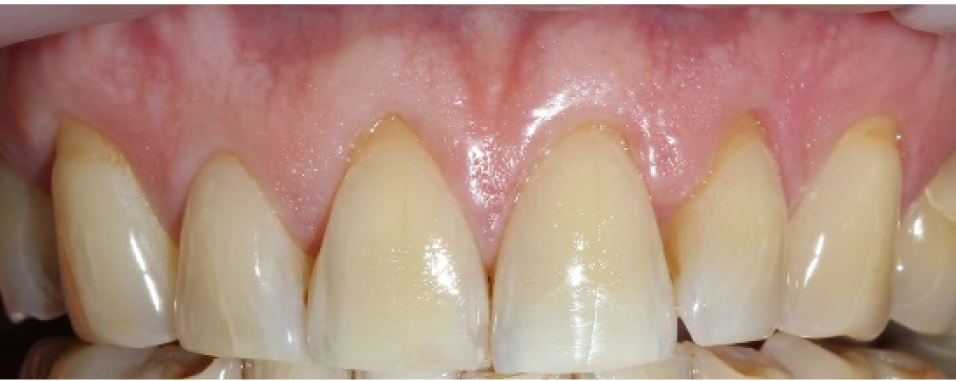

Во всех, без исключения, 20 клинических случаях было получено полное закрытие ранее выявленных рецессий [у 17 пациентов закрытие в пределах 3–4 мм (85 %), у 3 пациентов в пределах 2–3 мм (15 %)], причем данный результат был сохранен и в отдаленной перспективе – через 1, 2 и 3 года у всех пациентов отсутствовало рецидивирование рецессий, текстура и цвет мягких тканей не претерпели каких-либо изменений в сравнении с таковыми в области соседних зубов, где вмешательство не проводилось, ширина зоны кератинизированной прикрепленной десны в 14 случаях (70 %) увеличилась на 1,5 мм и в среднем составила 4,5 мм, в 6 случаях (30 %) увеличение произошло на 2,5 мм, а среднее значение ширины ЗКПД у данной группы пациентов – 5 мм (рис. 5).

Рис. 5. Отдаленный результат устранения рецессий на верхней челюсти